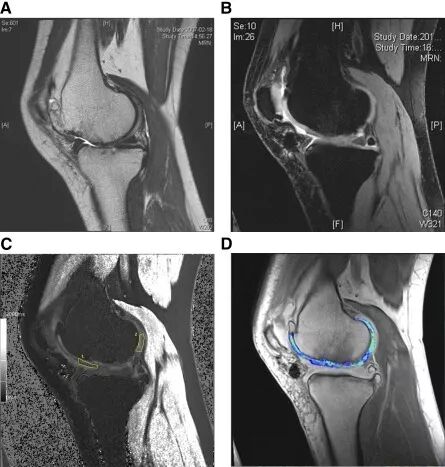

图片

△ 在MRI中可见3年后的软骨再生